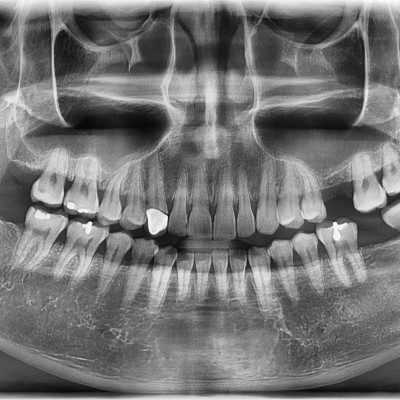

#28 사랑니 발치(#27포함) #28 사랑니 발치(#27 포함) 구강 외과 전문의가 당일 발치했습니다. ---------------------..

작성자 이턱이 작성일 03-11 조회 24